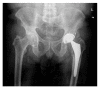

More than twenty years ago, hydroxyapatite (HA), calcium phosphate ceramics, was introduced as a coating for cementless hip prostheses. The choice of this ceramic is due to its composition being similar to organic apatite bone crystals. This ceramic is biocompatible, bioactive, and osteoconductive. These qualities facilitate the primary stability and osseointegration of implants. Our surgical experience includes the implantation of more than 4,000 cementless hydroxyapatite coated hip prostheses since 1990. The models implanted are coated with HA in the acetabulum and in the metaphyseal area of the stem. The results corresponding to survival and stability of implants were very satisfactory in the long-term. From our experience, HA-coated hip implants are a reliable alternative which can achieve long term survival, provided that certain requirements are met: good design selection, sound choice of bearing surfaces based on patient life expectancy, meticulous surgical technique, and indications based on adequate bone quality.